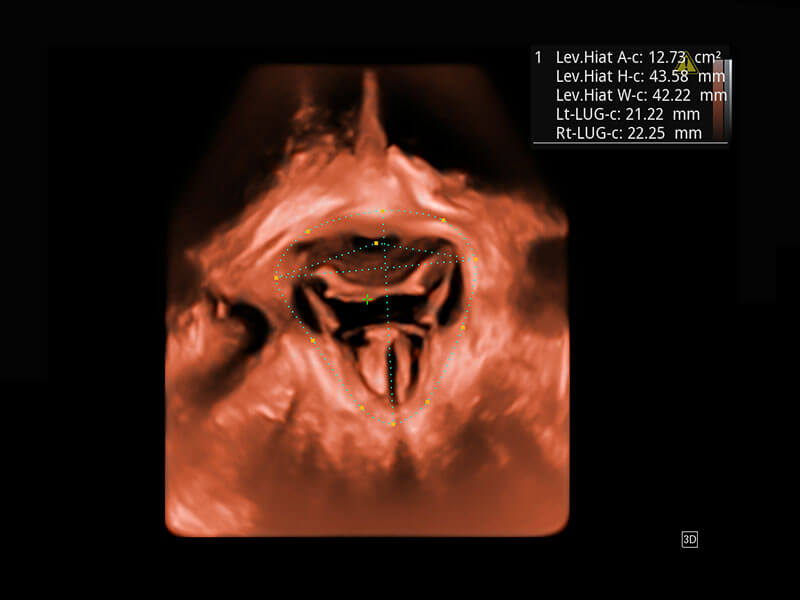

盆底超声

P60为盆底超声检查提供应用方案,多种腔内及腹部容积探头提供从二维、三维到四维的优异图像品质,实时快速三维容积数据获取,专业的测量工具包等人性化设计,为超声医生诊断提供有力保障。

S-Pelvic

能够简化盆底检查的操作流程,可在二维模式及三维成像模式下实现一键自动提取出标准切面、自动识别当前切面、自动测量,提升盆底检查的高效性,同时也能让青年医生快捷的获得准确的检查结果。

Lev.Hiat A-r: 16.33 cm2

Lev.Hiat H-r: 53.70 mm

Lev.Hiat W-r: 43.96 mm

Lt-LUG-r: 24.16 mm

Rt-LUG-r: 19.94 mm